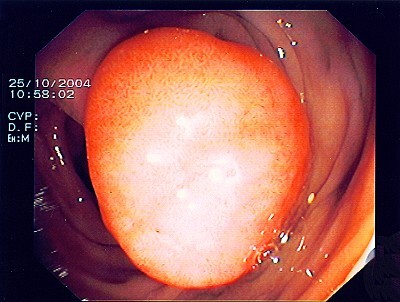

Großer Polyp des Dickdarmes